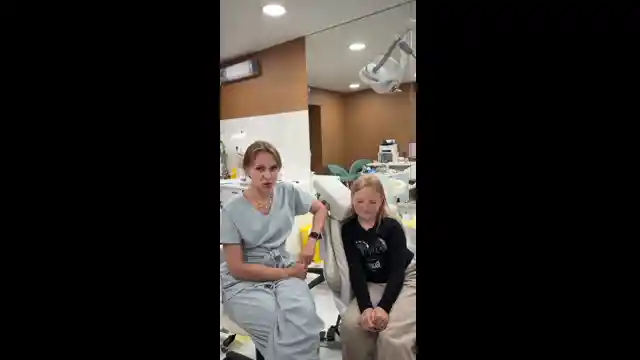

Лечащий врач

Медянцева Александра Алексеевна

Стоматолог - ортодонт, детский ортодонт. Ведущий специалист, заведующая ортодонтическим отделением.

9 лет практического опыта